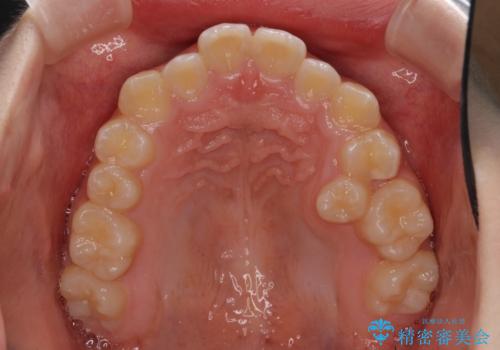

- 小児矯正の頃から診察を行っている患者様です。

上顎骨の幅が下顎骨よりも小さいので、拡大装置により骨幅を広げて上下関係を改善し、その後インビザラインにて歯並びを整えることとしました。

上下の骨幅を改善したことで、スムーズに歯列矯正を行うことができました。